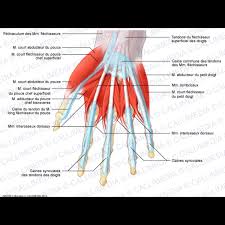

1181 × 1300 - gimolimpo.com

{"id":"Rohz-pKMmS4_0M:","isu":"gimolimpo.com","itg":0,"ity":"jpg","oh":1300,"ou":"http://www.gimolimpo.com/PAGINA%2062/musculosdorsales.jpg","ow":1181,"pt":"ANATOMIA

HUMANA","rid":"KhRkfq-OMAvQ7M","rmt":0,"rt":0,"ru":"http://www.gimolimpo.com/Paginas/ANATOMIA%20HUMANA.htm","s":"Visión

Frontal","sc":1,"th":236,"tu":"https://encrypted-tbn0.gstatic.com/images?q\u003dtbn:ANd9GcQbfHPY9kAjUYom1KfJZWZndoE6JCieaUeZv2ENDRKwDT_ucpXeRQ","tw":214}